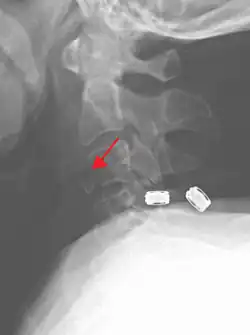

On CT scan or X-ray, a cervical fracture may be directly visualized. In addition, indirect signs of injury by the vertebral column are incongruities of the vertebral lines,[7] and/or increased thickness of the prevertebral space:[8]

-

X-ray of normal congruous vertebral lines